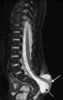

Anterior myelomeningocele

Spina bifida is a birth defect in which there is incomplete closing of the spine and the membranes around the spinal cord during early development in pregnancy. There are three main types: spina bifida occulta, meningocele and myelomeningocele. [Source: Wikipedia ]